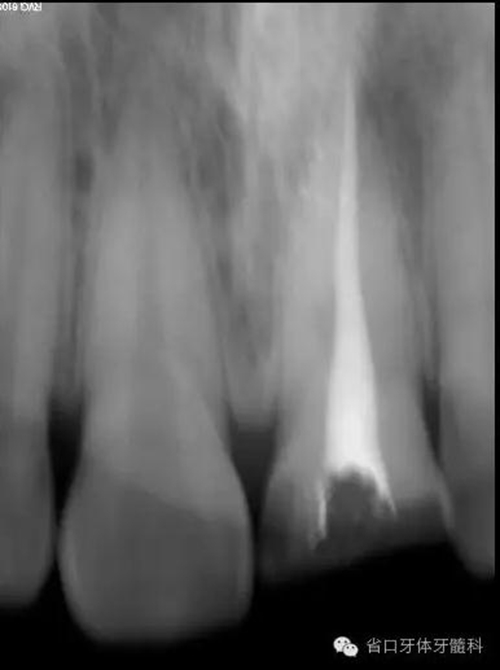

根充后X線片

術(shù)后x線片